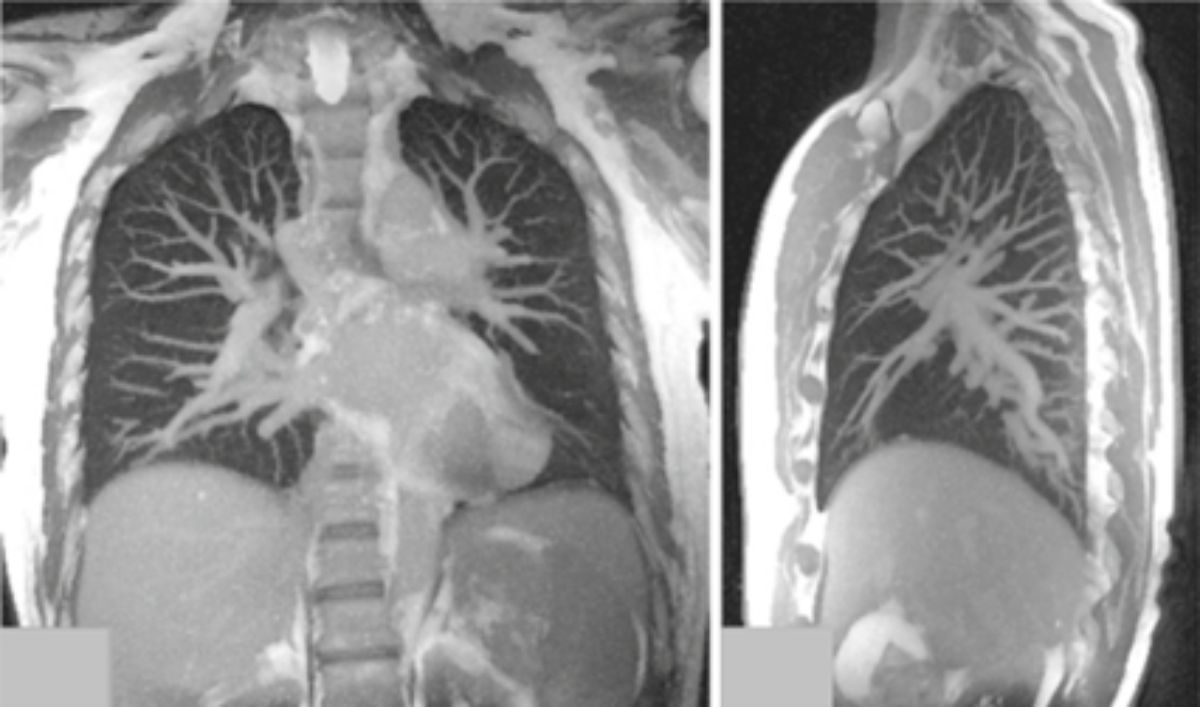

«Unsichtbar» – vergleichen wir Bild und Urteil zur Lungenbildgebung mittels Magnetresonanztomografie (MRT/MRI) zeigt sich, was unsere Forschung erreicht hat. Bis vor Kurzem galt, dass die Lunge mittels der MRT nicht dargestellt werden kann. Die Probleme, eindeutige, verwertbare Signale zu erhalten, liegen primär am hohen Luftanteil und der stetigen Bewegung des Organs. Unsere Wissenschaftler*innen der radiologischen Physik forschen dennoch seit Jahren an entsprechenden speziellen Verfahren – mit sichtbarem Erfolg.